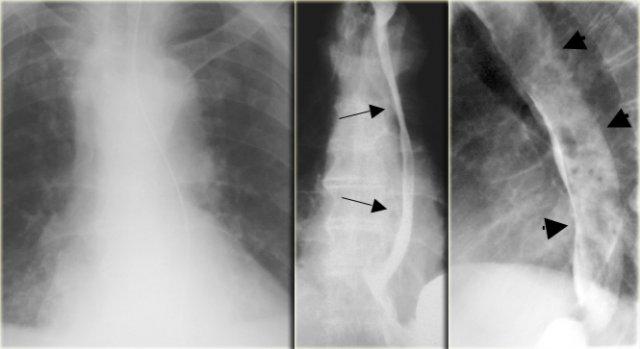

Bên trái là một trường hợp quai động mạch chủ đôi khác.

Phim X-quang ngực cho thấy đông đặc phổi phải do hít sặc ở trẻ 6 tuổi.

Quai phải và quai trái ấn lõm thực quản (mũi tên) ở các mức độ khác nhau.

Động mạch phổi trái bất thường: động mạch bất thường chạy giữa khí quản và thực quản, ấn lõm cả hai cấu trúc (mũi tên)

Động mạch phổi trái bất thường

Động mạch phổi trái bất thường ấn lõm mặt sau khí quản và mặt trước thực quản khi chạy giữa hai cấu trúc này.

Hẹp phế quản phải có thể gây ứ khí hoặc xẹp phổi.